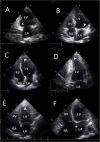

Methods: Patients with Chagas disease coming from an endemic area were selected from a large cohort (SaMi-Trop). A simplified echocardiogram with only three images was extracted from the conventional echocardiogram performed in this cohort. The images were evaluated by an observer who was blinded to the clinical and echocardiographic data, to determine the accuracy and reliability of FoCUS for cardiac assessment. The analysis constituted of 5 prespecified variables, dichotomized in absence or presence: left ventricular (LV) size and systolic function, right ventricular (RV) size and systolic function, and LV aneurysm.

Results: We included 725 patients with a mean age of 63.4 ± 12.3 years, 483 (67%) female. Abnormal electrocardiogram was observed in 81.5% of the patients. Left and right ventricular dysfunctions were found in 103 (14%) and 49 (7%) of the patients, respectively. Sensitivity, specificity, positive predictive value and negative predictive value were 84%, 94%, 70% and 97% for LV enlargement and 81%, 93%, 68% and 97% for LV systolic dysfunction, respectively, and 46%, 99%, 60% and 98% for RV dilatation, and 37%, 100%, 100% and 96% for RV dysfunction, respectively. Inter and intraobserver agreement were 61% and 87% for LV enlargement and 63% and 92% for LV dysfunction, respectively, and 50% and 49% for RV size and 46% and 79% for RV dysfunction, respectively. LV apical aneurysm was found in 45 patients (6.2%) with the lowest sensitivity of FoCUS study (11%; 95% CI 2-28%).